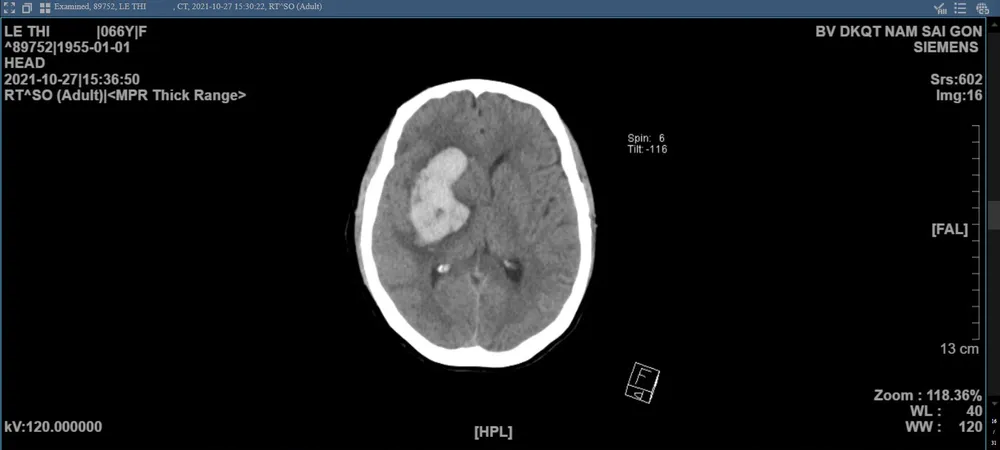

Nhanh chóng đánh giá tình trạng, tranh thủ tận dụng “thời điểm vàng” trong điều trị xuất huyết não đột quỵ, ThS.BS.CKII Đỗ Anh Vũ, Trưởng khoa Ngoại Thần kinh Bệnh viện ĐKQT Nam Sài Gòn nhanh chóng xử lý bước đầu, chỉ định chụp CT sọ não và phẫu thuật cấp cứu dẫn lưu máu tụ với hỗ trợ định vị 3 chiều Navigation. Kết quả CT ghi nhận có khối máu tụ trong não bên phải, phù não quanh tổn thương, chèn ép các cấu trúc lân cận, thoát vị não dưới liềm từ phải sang trái.

Hình ảnh CT não trước phẫu thuật